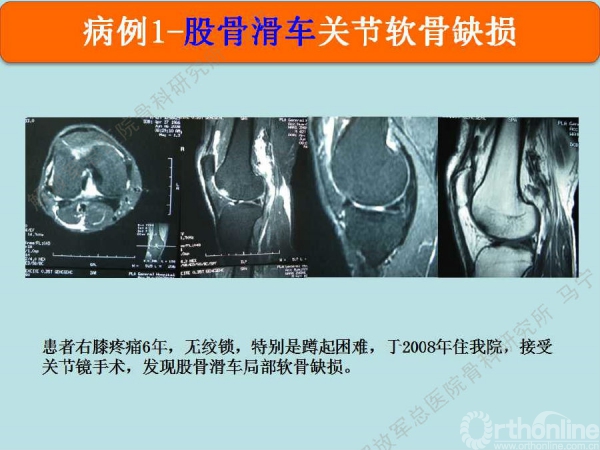

病例1

患者右膝疼痛6年,无绞锁,特别是蹲起困难,于2008年住我院,接受关节镜手术,发现股骨滑车局部软骨缺损。

术后8个月修复区的软骨厚度恢复理想,软骨下骨水肿信号不明显。术后16个月复查修复区的软骨没有太明显的变化。

患者是一个建筑公司的工长,每天要走很多路,对目前的效果很满意。